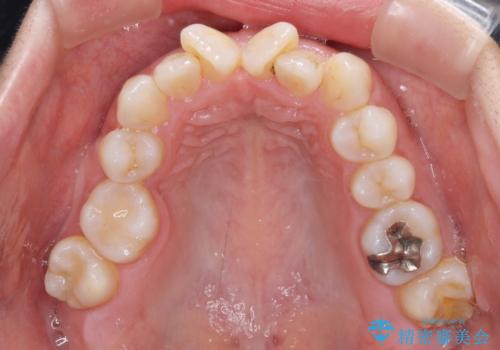

- 上下前歯のデコボコを気にして来院された患者様です。

右上と左下の小臼歯が1本ずつ欠損しており、奥歯の咬み合わせが乱れている状態でした。

バランスを取るために右下と左上の小臼歯を1本ずつ抜歯し、移動のための固定源としてアンカースクリューを利用してワイヤー装置による矯正治療を行うこととしました。